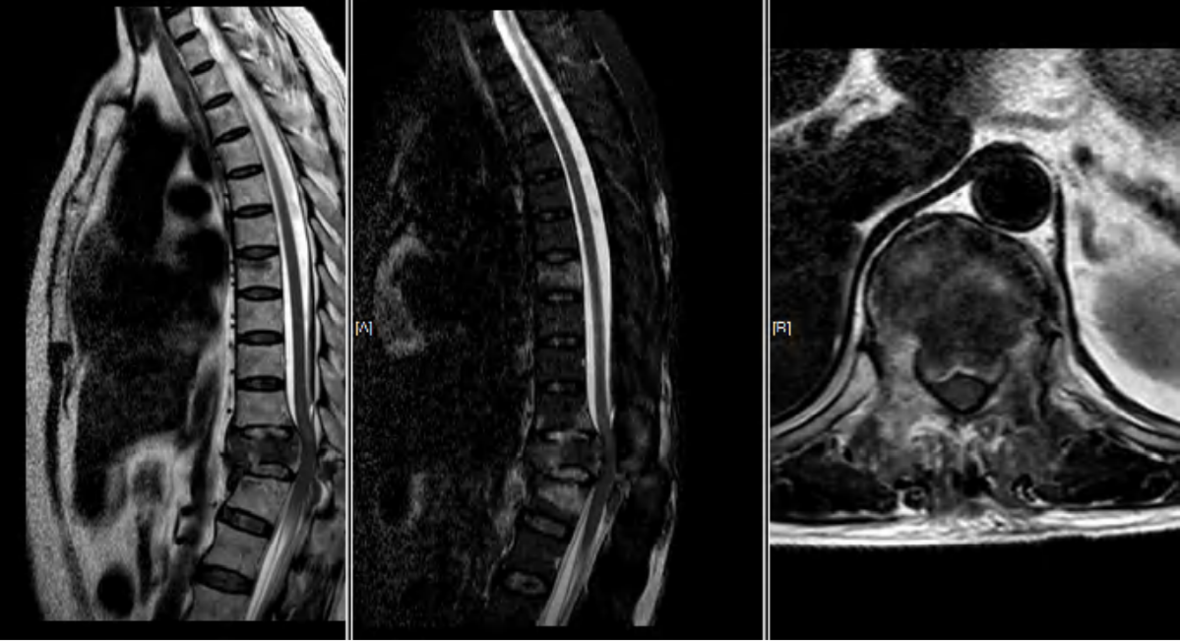

病例2车祸伤,完全性脊髓损伤

AO分型

- 分型:T12L1 C型;T12 B2型,L1 A1型

- 神经功能障碍分级:N4

- 修正参数:

- AO补充评分:C+N3(8+4) 12分

TLICS评分

- 骨折脱位(3分)

- 完全性神经损伤 (2分)

- PLC断裂(3分)

- 8分

载荷评分

- 碎裂大于60% 3分

- 后凸4~9度 2分

- 移位大于50% 3分

- 8分,合并脱位

治疗方案:手术治疗;后路手术,长节段固定